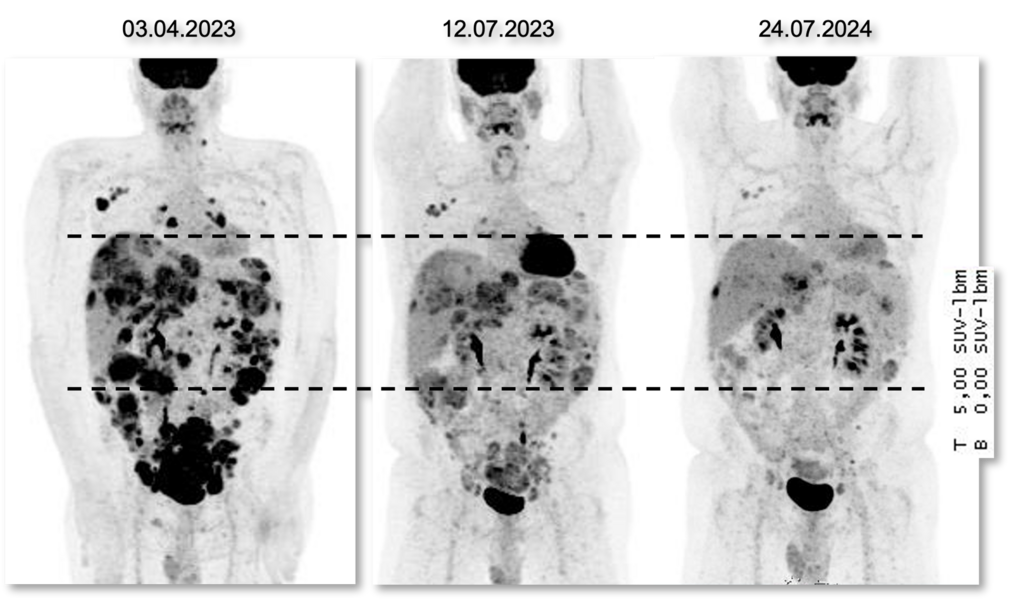

PET-Aufnahmen (Positronen-Emissions-Tomografie) eines Patienten zu drei Zeitpunkten zeigen ein sehr gutes Ansprechen auf das ADC Trastuzumab-Deruxtecan, das ungefähr 18 Monate angehalten hat.

Bemerkenswert ist, dass die Forschenden im Tumorgewebe häufig Proteine nachweisen konnten, die mit neuartigen, zielgerichteten Therapien adressiert werden können, insbesondere mit Antikörper-Wirkstoff-Konjugaten (ADC) oder mit therapeutischen Immunzellen, den CAR-T-Zellen. Mit einem ADC der jüngsten Generation, Trastuzumab Deruxtecan, wurde bei zwei Betroffenen eine ungewöhnlich lange anhaltende Tumorkontrolle erreicht, in einem Fall über zwei Jahre. Zusätzlich ergab die Studie, dass die Tumoren in acht von 30 Fällen erst durch die molekulare Analyse vollkommen richtig diagnostiziert werden konnten.